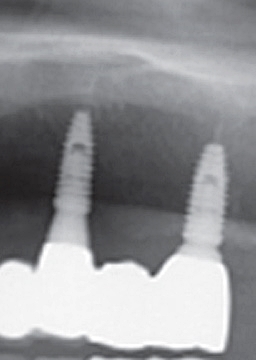

임플란트 시술을 성공적으로 마쳤다 하더라도 반드시 꾸준한 사후관리가 이루어지는 것이 중요하였어요. 이러한 과정들은 반드시 꼼꼼한 사전 과정을 거친 후에 환자에게 맞는 임플란트 시술이 진행되어야 하였어요. 그래야지만 안전한 시술이 가능해질 수 있었어요.

이러한 풀아치 임플란트 시술은 기존의 임플란트 시술과 매우 흡사하다 보니, 구강 구조 및 잇몸의 양을 꼼꼼히 체크하시어 이루어지는 것이 중요하였어요. 또한 주변 신경과 혈관의 위치를 제대로 확인한 후에 치료가 이루어져야지만 안전한 시술이 가능할 수 있었어요.

그렇다 보니 이러한 임플란트 시술은 치료 경험이 다분한 전문 의료진이 있는 반포치과를 선택하셔서 내원하시어 이루어지는 것이 중요하였어요. 그렇게만 된다면 무치악으로 인해 완전히 잃어버렸던 저작기능을 충분히 회복할 수 있겠어요.